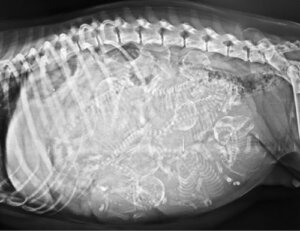

L’aspetto del cucciolo non potrebbe essere più atipico: con il pelo bianco e di piccola taglia, questo cane aveva un enorme occhio sulla fronte e 2 grandi lingue sporgenti su ciascun lato della bocca. Poiché l’apparato oculare occupava così tanto spazio, non aveva né il muso, né il naso.

Per quanto sorprendente possa sembrare, la storia di questo cane non è unica nel regno animale. La ciclopia è una malformazione congenita che si verifica in molti mammiferi, caratterizzata dalla presenza di un occhio centrale risultante dalla fusione dei 2 occhi e dell’oloprosencefalia allobare, cioè il mancato sviluppo degli emisferi cerebrali.